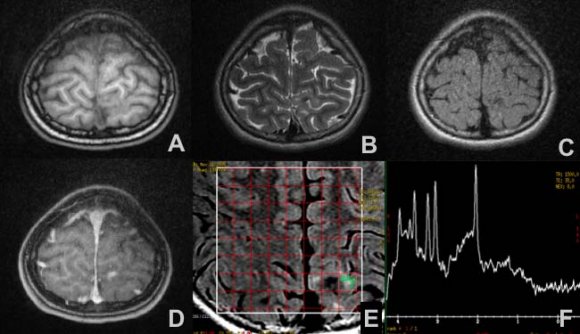

Telemetric video and magnetic resonance show epilepsy initiating in the left hemisphere with parietal epileptogenic zone in relation to hypo-intense media lesion in T1 (Figure 1 a), hyper-intense in T2 (Figure 1 b), hypo-intense in FLAIR (Fluid attenuation inversion recovery) (Figure 1 c) with an anomaly in the configuration of cerebral tissue, without signs of bleeding, enhanced by the administration of contrast (Figure 1 d) leading to a consideration of low grade glial lesion as a possible diagnosis, for which reason magnetic resonance spectroscopy is used to complement the study, evidencing diminished N-acetylaspartate peak, increased myoinositol with inverted lactate peak (Figure 1 e, f) suggesting meningioangiomatosis associated with cortical dysplasia as opposed to oligodendroglioma.

Although findings from imaging studies are variable, single lesions with calcification are commonly observed in tomography studies, as are signal alterations in magnetic resonance that are consistent with hypo-intensity in T1, hyper-intensity in T2 and the FLAIR, and enhancements with the administration of contrast in T1 (5,6): despite the high resolution images, it is difficult at this time to identify the presence of focal cortical dysplasia type IIIc associated with MA in preoperative studies (1). Magnetic resonance spectroscopy in the analysis of the spectrum of metabolites describes increased elevation of choline peak (cho) with a reduction of N-acetylaspartate peak (NAA), which is related to a cellular proliferation presumed to derive from meningothelial cells and/or fibroblasts around blood vessels in the cortex, which are associated with studies by positron emission tomography (PET) documenting focal hypermetabolism which may be suggested as a differential diagnosis MA (7). The principle differential diagnoses are low grade gliomas, arteriovenous malformations, and invasive malignant meningioma (4).